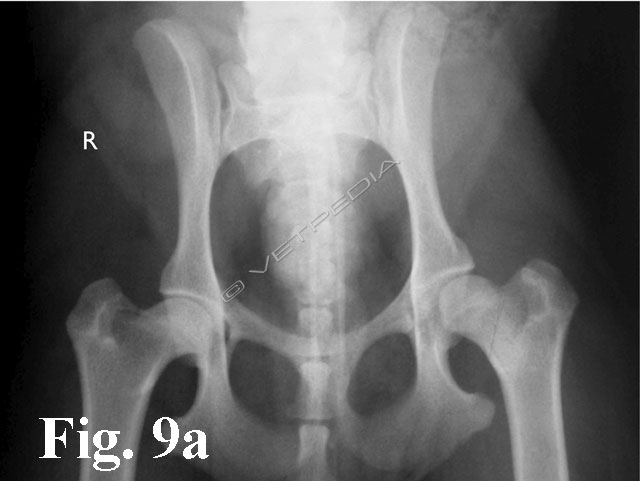

{{/_source.additionalInfo}}La necrosi asettica della testa del femore è anche denominata malattia di Legg Calvè Perthes e necrosi avascolare della testa del femore. Si tratta di un'affezione ortopedica coinvolgente l’articolazione coxofemorale di cani di razza toy o di piccola taglia durante il periodo dell’accrescimento, ad interessamento più frequentemente monola